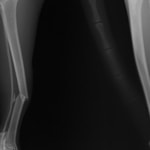

トイプードル 右遠位橈尺骨短斜骨折のALPSによる内固定